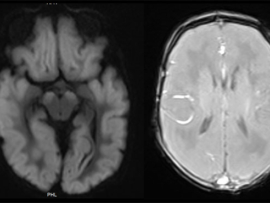

A term, appropriate-for-gestational-age neonate with normal APGAR scores and no history of perinatal hypoxia presented with seizures on day 2 of life.